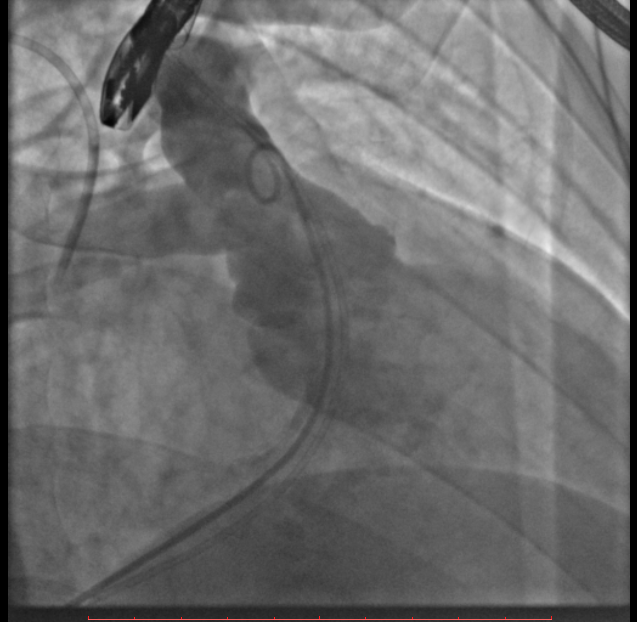

术中测量患者基础主动脉、肺动脉、右心室压力分别为111/58mmHg、31/4/13mmHg、34/1/6mmHg,通过肺动脉造影,术中测量球囊内径为32mm(见图二),选择36-25mm VENUS-P肺动脉瓣膜,在肺动脉造影指引下逐步打开瓣膜。考虑到患者肺动脉分叉较短,存在瓣膜释放后移位风险,故选择高位释放法(图三)。但释放瓣膜后造影提示右肺动脉开口局部被阻挡(图四),复测患者主肺动脉、左肺动脉、右肺动脉压力分别为57/13/25mmHg、55/12/24mmHg、27/7/14mmHg。

图三:考虑到患者肺动脉分叉较短,选择高位释放法